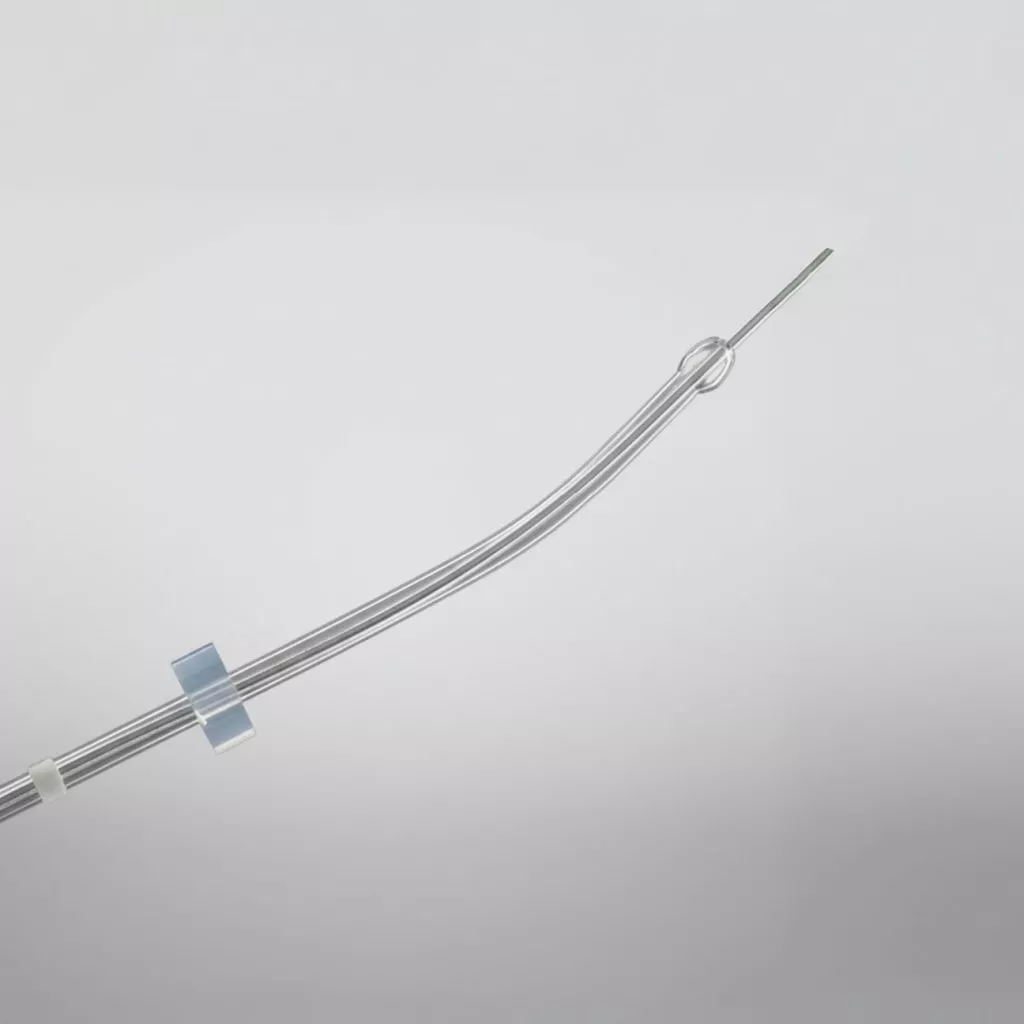

Guardia™ Access Nano Embryo Transfer Catheter

Guardia™ Access Embryo Transfer Catheter with Internal Support Cannula

Guardia™ Obturator

Guardia™ Access Malleable Obturator

Soft-Pass™ Malleable Obturator

Guardia™ AccessET Embryo Transfer Catheter

Guardia™ Access Embryo Transfer Catheter